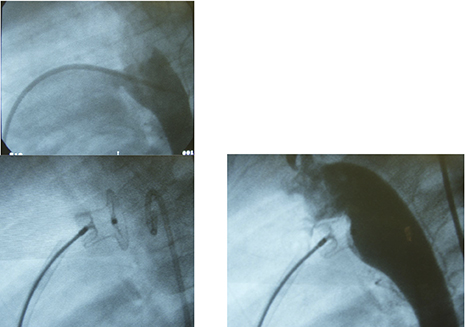

This picture shows a case of big PDA with a diameter of 8mm, which was finally closed using 14 coils in 3 sessions in this visit. I believe this is the largest one which can be closed with coils. We reported this case in the international conference.

The arrow indicates this case just before discharge, when she had become very active.